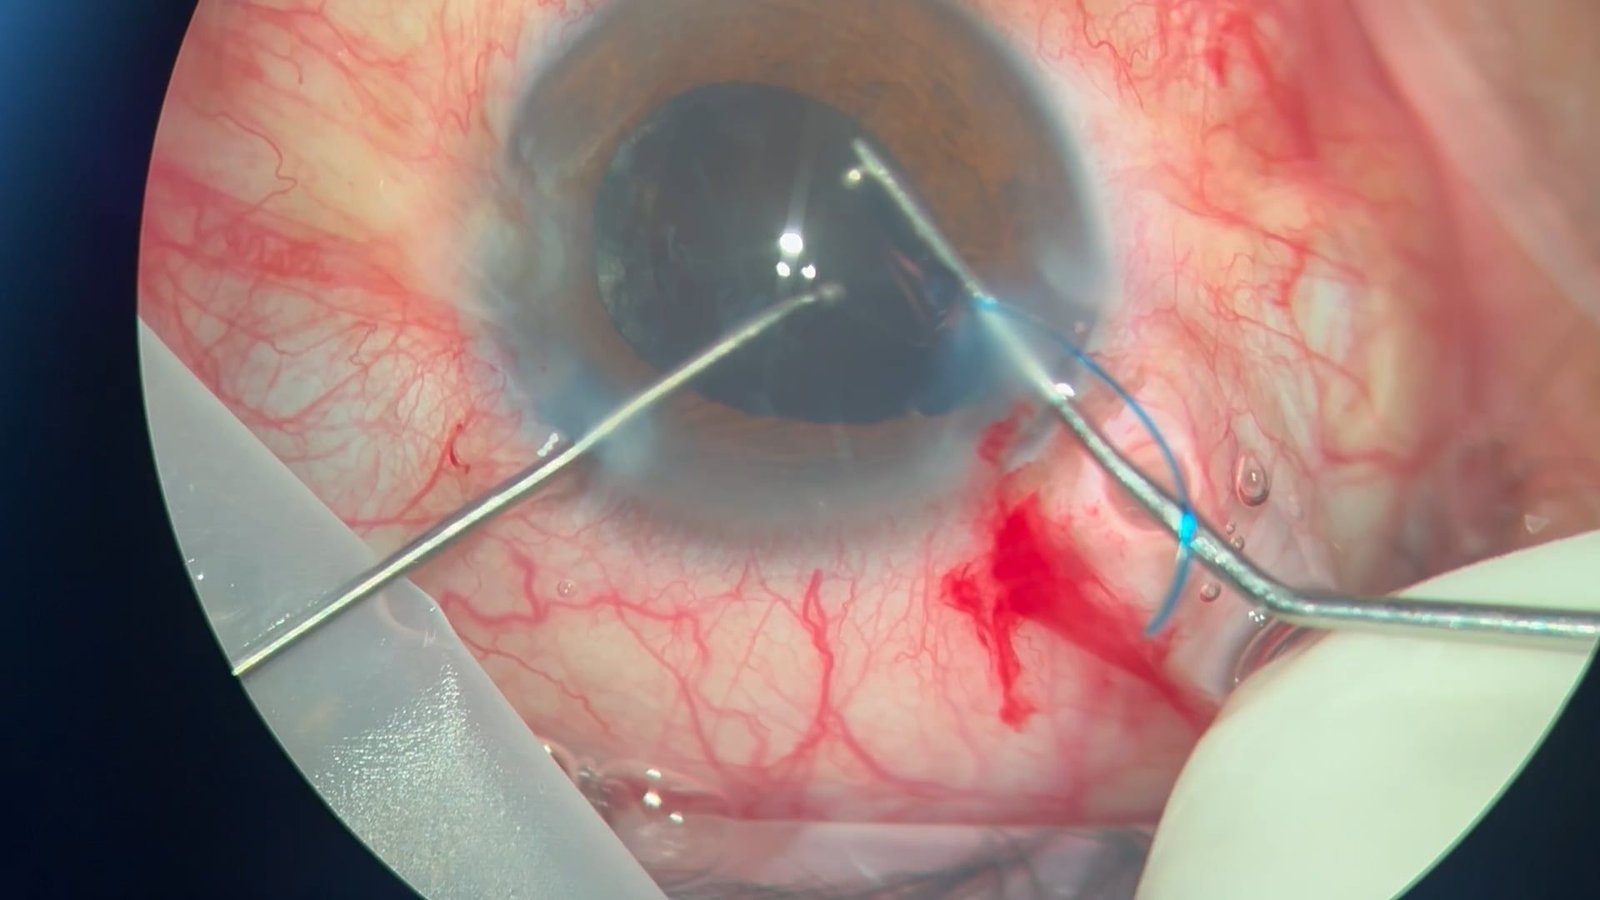

Correción de afaquia con técnica Yamane y cerclaj…

Diego Araujo, Fátima Romero, Sebastián Ortiz